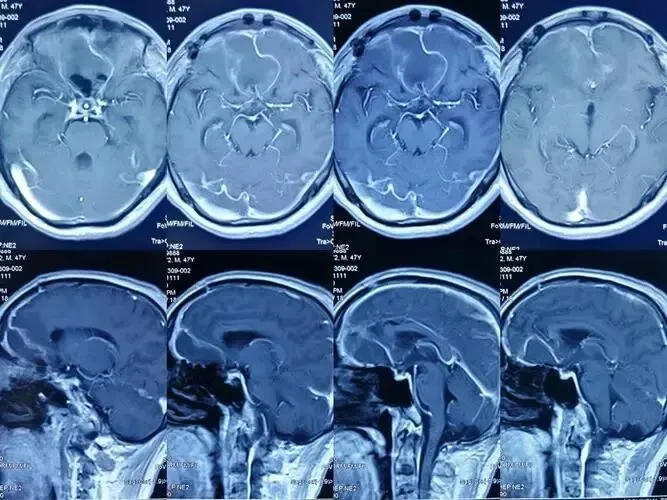

术前评估和术后护理:手术治疗前需进行详细的术前评估,包括影像学检查、脑电图监测等。术后仍需继续抗癫痫药物治疗,并定期随访。